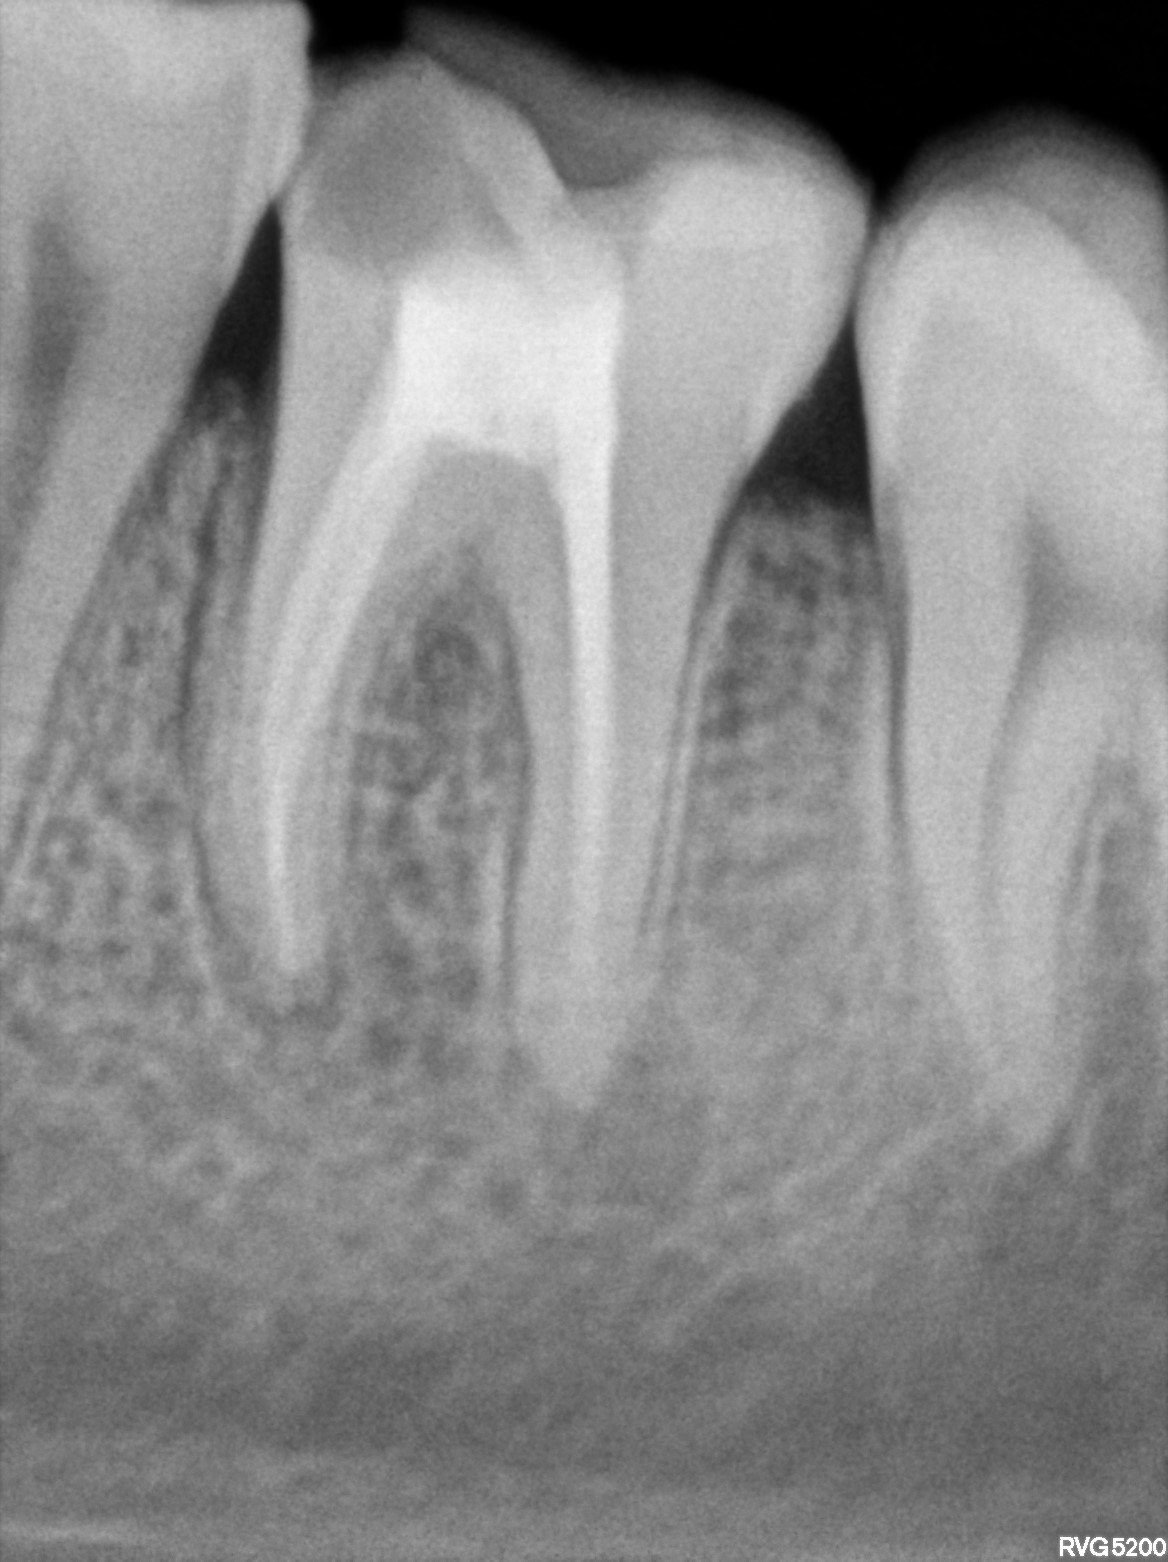

Dental Radiographs FHIR: DocumentReference · LOINC 24641-7

46.jpg

24641-7

R61.jpg